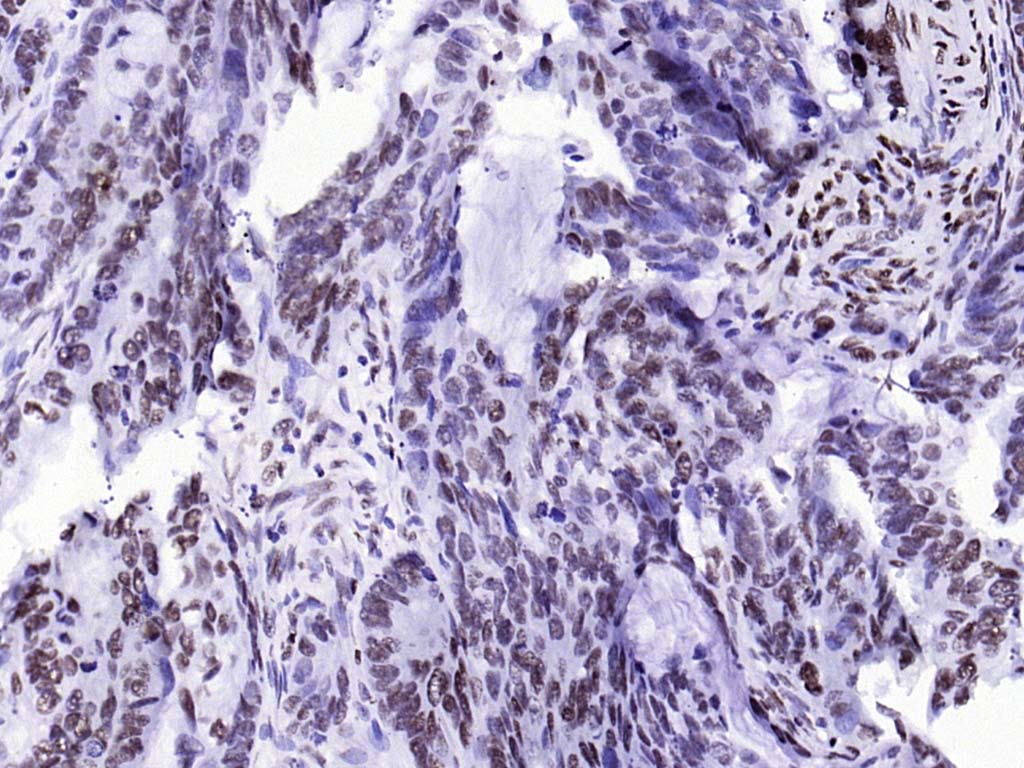

| 产品应用 | WB=1:200-1000, IHC-P=1:100-400, IHC-F=1:100-400, ICC/IF=1:100-500, IF=1:100-500, ELISA=1:5000-10000 Not yet tested in other applications. |

| {IHC-P} | {1:100-400} |